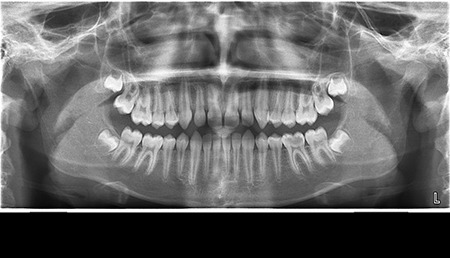

- Цифрова панорамна рентгенографія (ортопантомограма) – дає цілісне зображення всієї щелепно-лицевої системи.

Що ви уявляєте, коли лікар говорить про ортопантомограму? Насправді, це знімок усієї зубощелепної системи, який охоплює обидві щелепи, гайморові пазухи та скронево-нижньощелепні суглоби. Таке оглядове фото дозволяє стоматологу отримати загальне уявлення про стан зубів, кісткових структур та навколишніх тканин.

Ортопантомограма Полтава є незамінною при первинній діагностиці, коли потрібно оцінити загальний стан ротової порожнини. Її призначають у наступних випадках:

- для моніторингу росту та прорізування зубів у дітей.